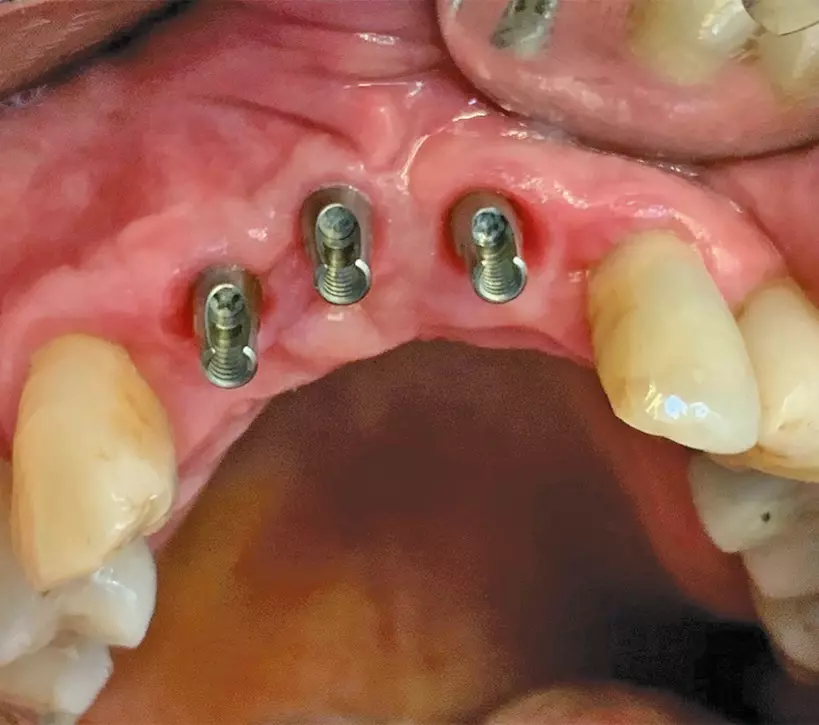

- Verschraubung der Restauration mit dem Abutment

Ein weiterer Vorteil ist darin zu sehen, dass nur eine Verschraubungseinheit vorliegt, deren Schraubenkopf zudem tief an der Basis des Abutments angeordnet ist und einen relativ kleinen Durchmesser aufweist. Damit lässt sich der okklusale Zugang in gleicher Weise wie oben erwähnt verschließen und ein günstiger kosmetischer Effekt erzielen (Abb. 5a-d).